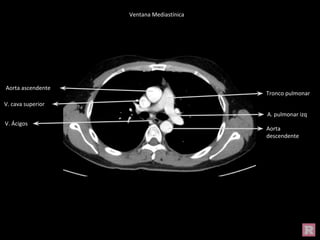

Aorta ascendente

Tronco pulmonar

V. cava superior

Aorta

descendente

A. pulmonar izq

V. Ácigos